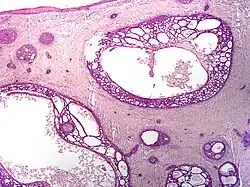

Nodular basal-cell carcinoma

.jpg)

Nodular basal-cell carcinoma (also known as "classic basal-cell carcinoma") accounts for 50% of all BCC.[29] It most commonly occurs on the sun-exposed areas of the head and neck.[30]: 748 [31]: 646 Histopathology shows aggregates of basaloid cells with well-defined borders, showing a peripheral palisading of cells and one or more typical clefts.[29] Such clefts are caused by shrinkage of mucin during tissue fixation and staining.[32] Central necrosis with eosinophilic, granular features may also be present, as well as mucin. The heavy aggregates of mucin determine a cystic structure. Calcification may also be present, especially in long-standing lesions.[29] Mitotic activity is usually not so evident, but a high mitotic rate may be present in more aggressive lesions.[29] Adenoidal BCC can be classified as a variant of NBCC, characterized by basaloid cells with a reticulated configuration extending into the dermis.[29]